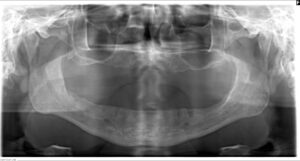

初診時